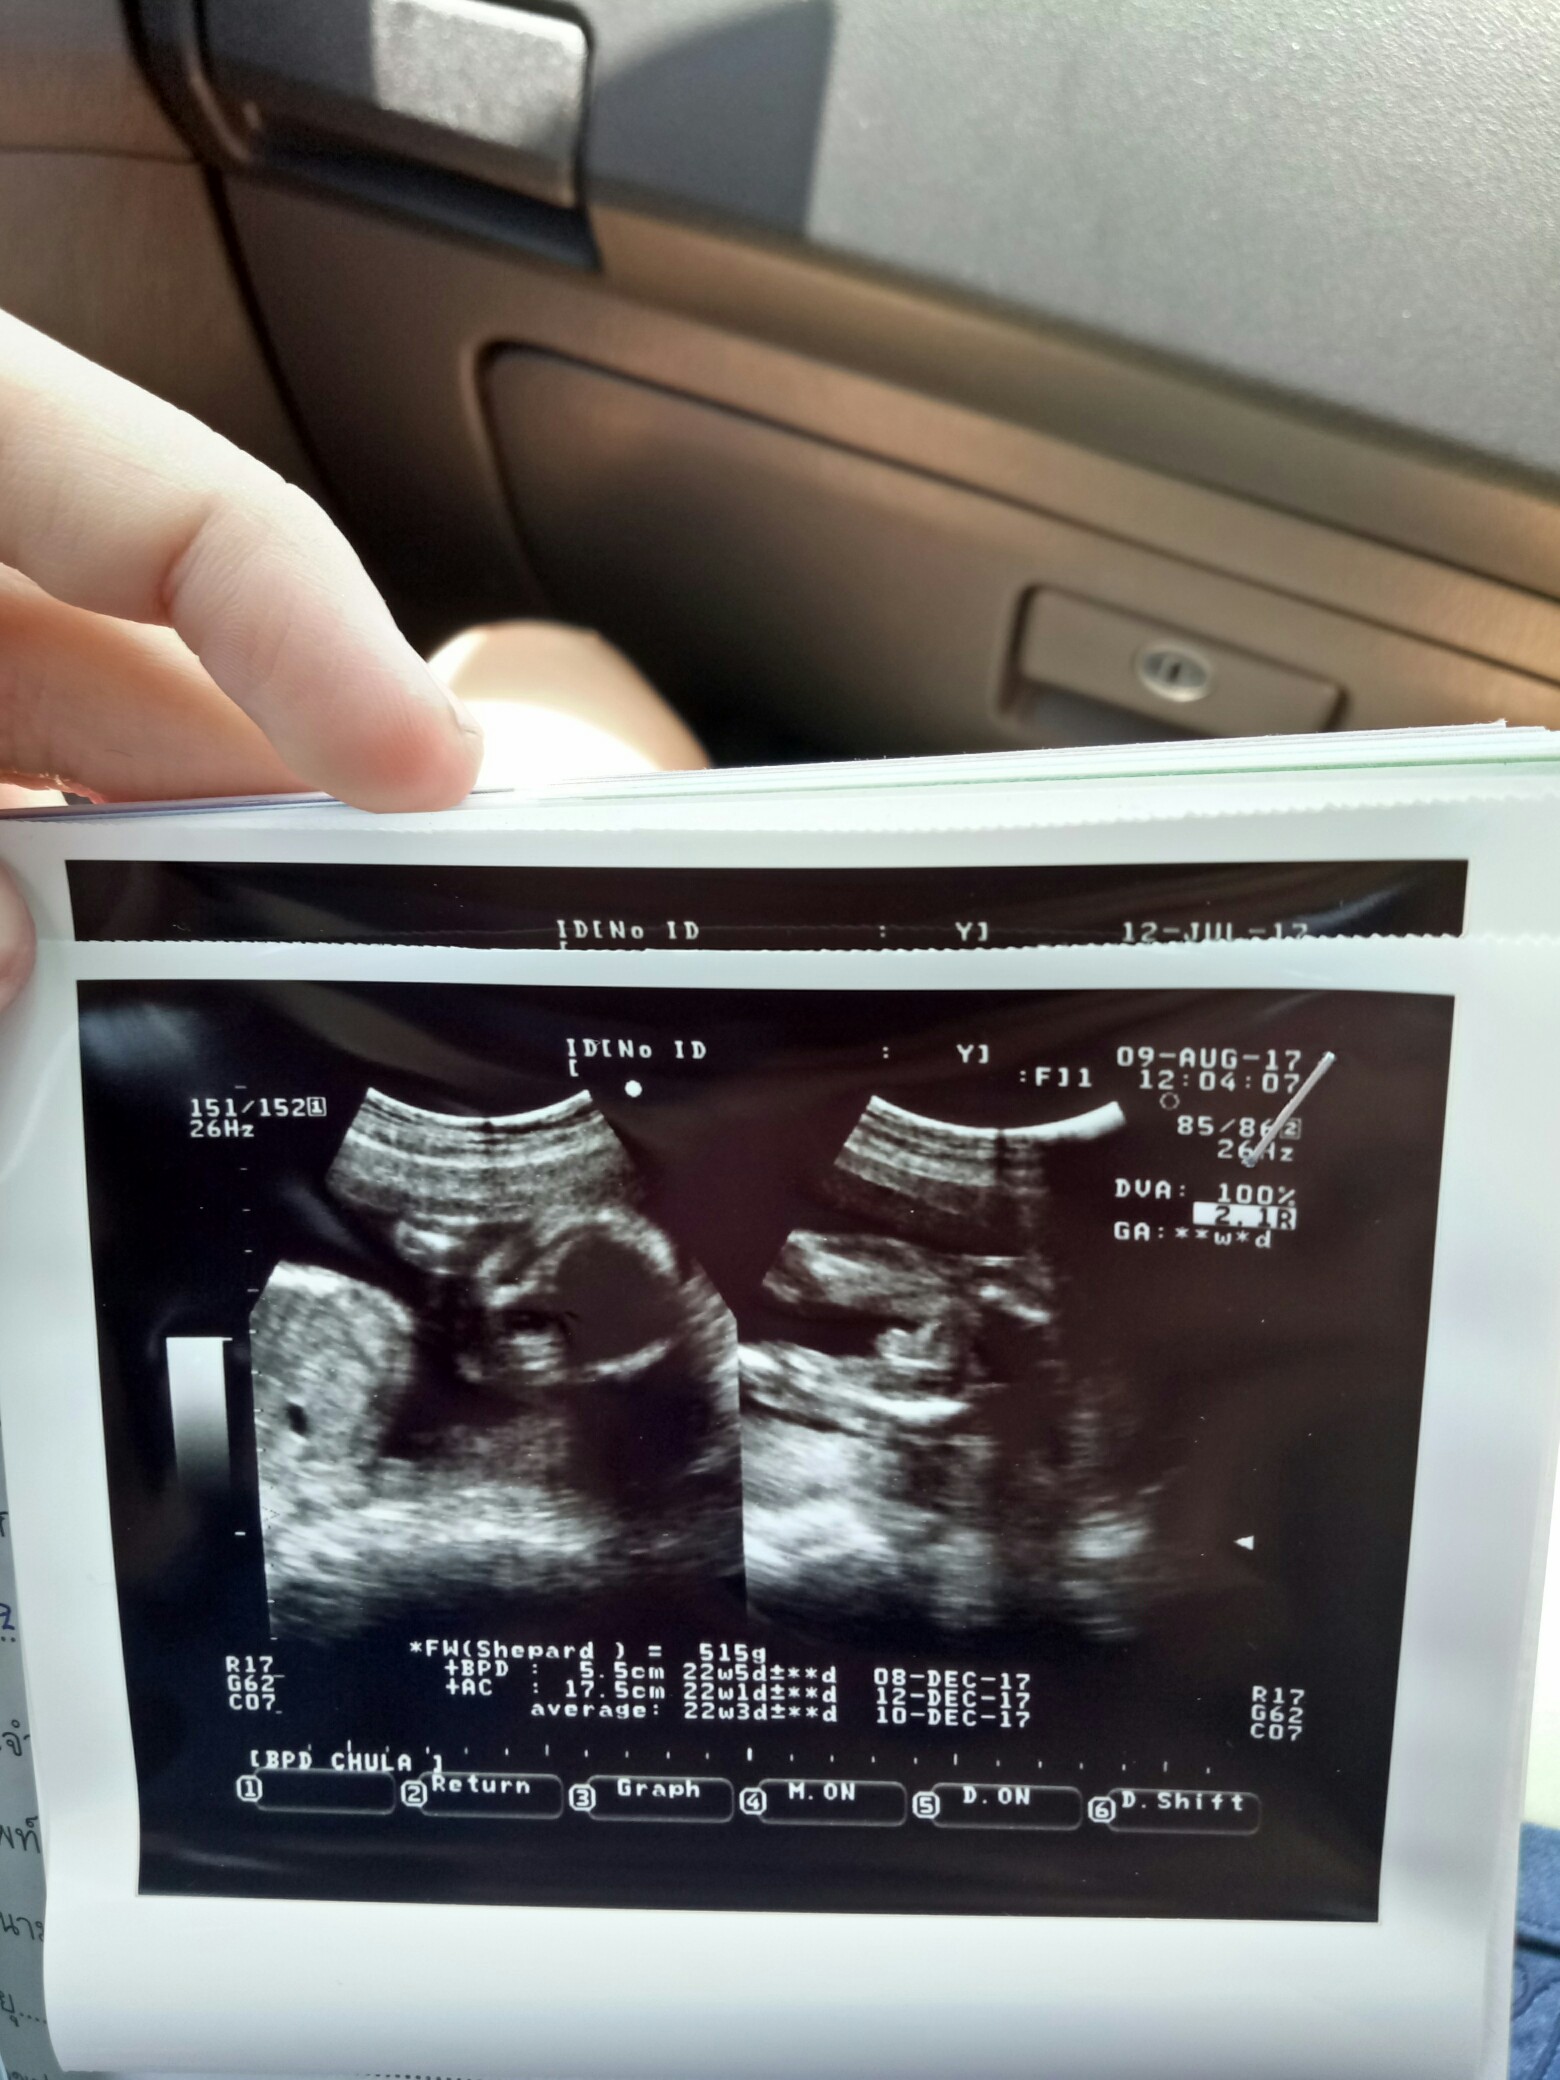

ช่วยดูผลอัลตร้าซาวด์หน่อยค่ะ ว่าเพศอะไร มีรูป